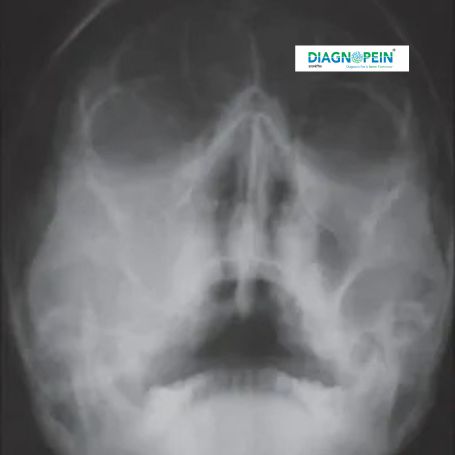

CT PNS (Computed Tomography of the Paranasal Sinuses) is a specialized imaging test that provides detailed pictures of the sinus cavities, nasal passages, and surrounding structures. It helps diagnose sinus-related problems such as infections, blockages, inflammation, and structural abnormalities.

At Diagnopein Nashik, our advanced CT scan facility captures precise cross-sectional images of the sinuses, enabling accurate diagnosis for ENT specialists and physicians. The scan is quick, painless, and highly detailed compared to traditional X-rays.

Proper CT PNS placement during scanning ensures correct visualization of the sinuses and nasal pathways. The patient’s head is carefully positioned to capture optimal axial and coronal sinus planes. This positioning allows radiologists to evaluate even subtle abnormalities in the ethmoid, maxillary, sphenoid, and frontal sinuses.